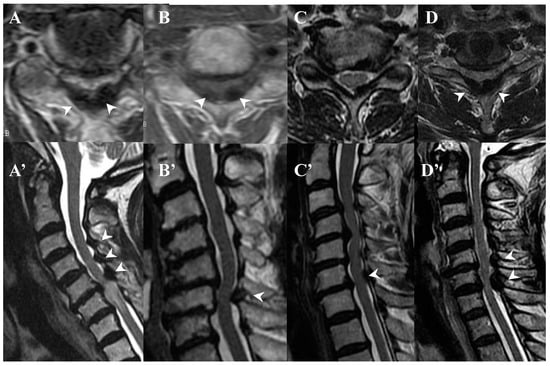

3.3. Neuroradiological Findings (Figure 3, Figure 4, Figure 5 and Figure 6; Table 3)

4.2. Comparison of Neuroradiological Findings between CLF and OLF (Figure 3, Figure 4, Figure 5 and Figure 6; Table 3)